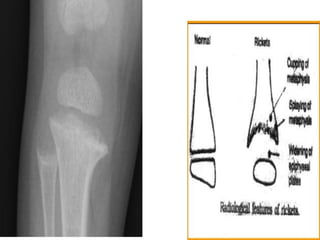

• Rickets is deficient mineralization at the growth plate of long bones,

resulting in growth retardation. If the underlying condition is not

treated, bone deformity occurs, typically causing bowed legs and

thickening of the ends of long bones.

• Only occurs in growing children before fusion of the epiphyses,

typically affecting wrists, knees, and costochondral junctions.